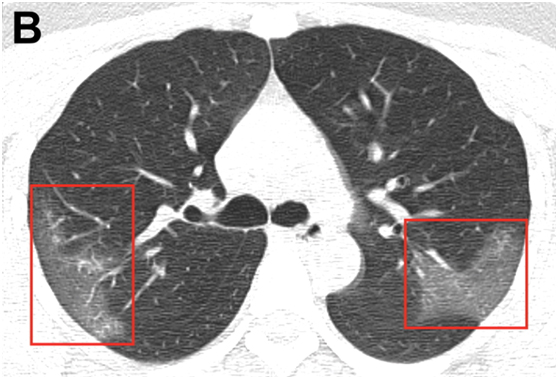

目前,放射科医师们正在努力寻找该病毒在医学影像中的表现。1月31日,北美放射学会(RSNA)在其《放射学》杂志上发表了关于冠状病毒(2019-nCoV)的首批影像研究。这是一个来自中国的案例研究,解读了一名33岁新冠肺炎女性患者的计算机断层成像(CT)。

图B:经过三天的治疗,并结合干扰素吸入,该患者临床表现更差,复查胸部CT显示右上叶后段及左上叶顶端后段进行性毛玻璃样混浊。

研究指出,影像学检查是2019-nCoV诊断的关键组成部分。双侧对称的肺周混浊是2019新型冠状病毒肺炎的常见CT表现。早期疾病识别不仅对及时治疗至关重要,而且对患者隔离和有效的公共卫生控制和应对也至关重要。